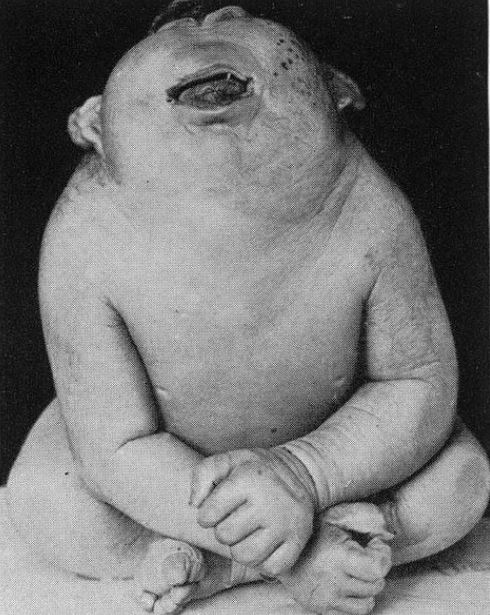

Trẻ mắc cyclopia thì khác. Quá trình hình thành gương mặt của chúng bị "lỗi", khiến cho 2 mắt không thể phân chia, chỉ để lại một con mắt duy nhất ngay chính giữa khuôn mặt. Mũi và miệng cũng không xuất hiện.

Trẻ mắc bệnh cyclopia.

Cũng như mắt, não của trẻ mắc cyclopia cũng không thể phân chia thành 2 bán cầu như người bình thường. Hậu quả, những em bé thiếu may mắn này thường không có cơ hội ra đời, mà thường chết vì sảy thai, hoặc do các bậc cha mẹ phải nạo phá thai.

Thậm chí ngay cả khi sống sót đến khi sinh nở, những đứa trẻ này cũng chết trong vòng vài giờ đến vài ngày. Nguyên nhân chết không giống nhau, nhưng thường là do những đứa trẻ này không có miệng, hoặc do hệ hô hấp bị suy yếu, không hoạt động bình thường được.